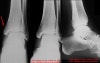

삼과골절(trimalleolar fracture)은 뒤쪽 복사뼈 골절이 포함된 경우입니다. 발목의 뒤쪽탈구에서도 삼과골절이 동반될 수 있으며, 이런 경우를 '삼과골절-탈구'라고 합니다.

AP, lateral, Mortise view를 보면 대부분의 골절이 진단됩니다.

돌림손상 시에는 거골 바깥쪽 관절면의 골연골성 골절이 일어날 수 있습니다. Mortise view에서 가장 잘 나타나며 복합골절 평가 시에는 CT가 필요할 수 있습니다.

X-ray : 삼과 골절(Trimalleolar fracture)